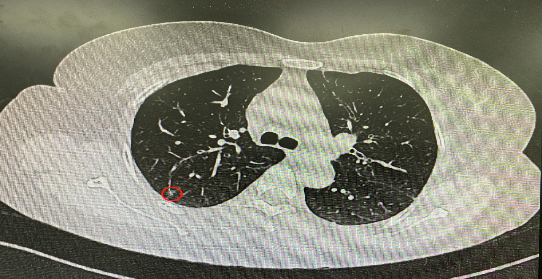

今年54歲的李女士(化名)7月初突然出現(xiàn)右上部腹痛,起初并未在意,以為稍作休息就會好轉(zhuǎn),但疼痛卻并未消退,持續(xù)了一個(gè)星期。李女士實(shí)在難以忍受,才在家人陪伴下來到西安國際醫(yī)學(xué)中心醫(yī)院就診。胸外科二病區(qū)崔凱主任接診患者后,詳細(xì)詢問病情并查閱檢查資料,經(jīng)胸部HRCT檢查,結(jié)果提示:右肺上葉后段混合密度結(jié)節(jié)影,考慮原位癌可能,即將患者收入胸腔外科二病區(qū)住院治療。

經(jīng)與患者家屬溝通,崔凱主任決定行外科手術(shù)治療。為達(dá)到精準(zhǔn)切除,術(shù)前需進(jìn)行肺小結(jié)節(jié)切除前定位。由于結(jié)節(jié)位于右肺上葉后段,傳統(tǒng)經(jīng)胸外穿刺術(shù)無法抵達(dá)病灶。崔凱主任與呼吸內(nèi)科一病區(qū)歐陽海峰主任討論后,決定擬行LungPro全肺診療導(dǎo)航下染色定位。即術(shù)前通過Lung Pro導(dǎo)航規(guī)劃染色位置,經(jīng)Lung Pro實(shí)時(shí)引導(dǎo)支氣管鏡抵達(dá)既定位置,注入亞甲藍(lán)染色劑標(biāo)記結(jié)節(jié)位置。

使用術(shù)前規(guī)劃系統(tǒng)重建全肺3D模型,并于外科醫(yī)生討論染色位置,最終確定標(biāo)記染色點(diǎn)—右肺上葉后段b亞段(RB2b)。術(shù)中使用P290(4.9mm外徑)標(biāo)準(zhǔn)支氣管鏡,根據(jù)導(dǎo)航術(shù)前規(guī)劃路徑,Lung Pro實(shí)時(shí)導(dǎo)航下,GS鞘管進(jìn)入RB2b遠(yuǎn)端官腔外病灶并注射亞甲藍(lán)染色劑。

一切準(zhǔn)備就緒,7月15日,崔凱主任團(tuán)隊(duì)聯(lián)合歐陽海峰主任團(tuán)隊(duì)為患者行單孔胸腔鏡下右肺上葉后段切除術(shù),手術(shù)用時(shí)128分鐘順利完成。進(jìn)入胸腔后,亞甲藍(lán)染色部位明顯,患者發(fā)生癌變的右肺上葉后段被成功切除。術(shù)后標(biāo)本根據(jù)染色部位迅速找到結(jié)節(jié),剖開位置兼染色位置和病灶完全符合,行術(shù)中冰凍后快速送病理檢查。經(jīng)術(shù)后病理檢查,明確診斷為(右肺上葉)原位腺癌。